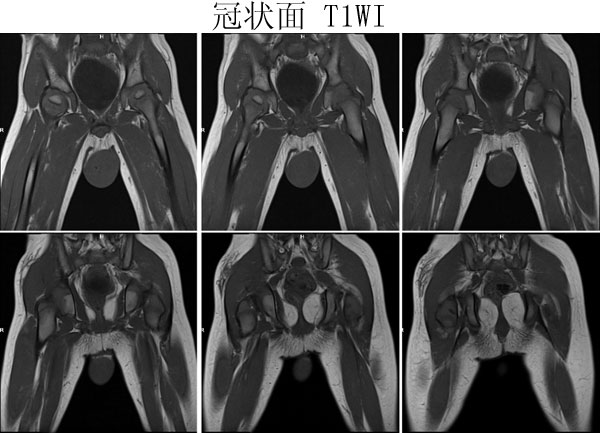

(广东同江医院的病例)男,2岁。左侧睾丸肿大3月,开始发现时红枣大,逐渐增大,现鸡蛋大小,表面光滑,无压痛,质地中等。

病理诊断 :(左侧)

睾丸胚胎性横纹肌肉瘤

,瘤组织局部浸润附睾组织,精索残端组织内未见瘤组织浸润。